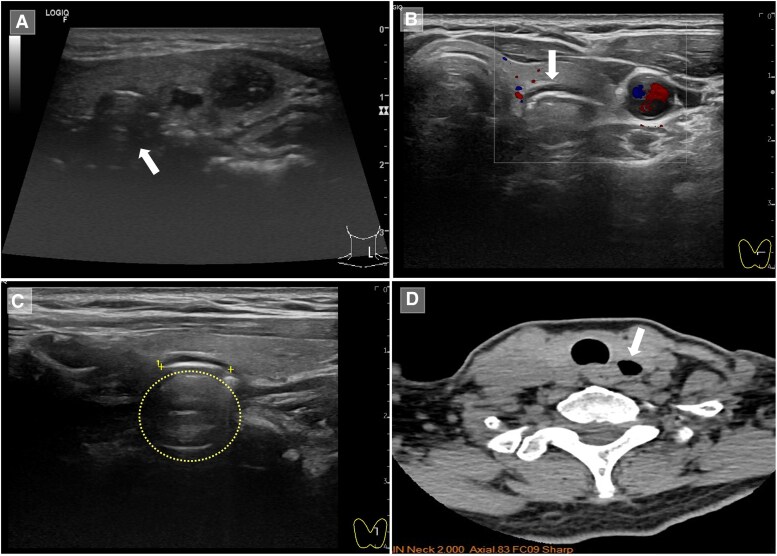

Zenker憩室伪装成甲状腺结节。

Zenker Diverticulum Masquerading as a Thyroid Nodule.